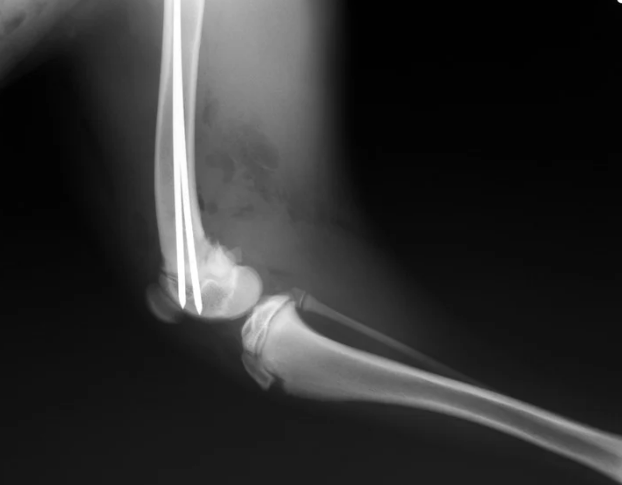

1.4 통증성 떨림 — 관절이나 인대 문제

한쪽 다리만 들거나, 만졌을 때 움찔하는 경우라면 단순 피로가 아닙니다. 이건 통증성 떨림이에요.

슬개골 탈구, 고관절 이형성증, 관절염 등 관절 질환은 통증 때문에 다리에 미세한 떨림이 생깁니다. 특히 노령견이나 소형견이라면 관절 건강을 꼭 점검해야 해요.